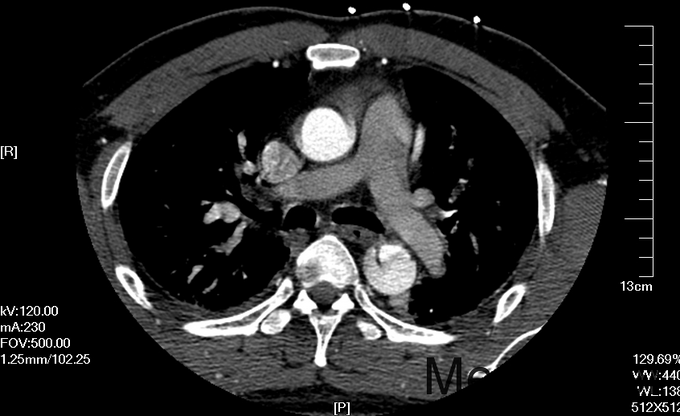

入院查体:体温36.5℃,脉搏90次/分,规则,呼吸18次/分,规则,血压150/80mmHg,胸廓正常,无胸骨叩痛。呼吸运动正常,语颤正常,无胸膜摩擦感,无皮下捻发感,叩诊正常清音,肺下界正常,双肺呼吸音粗,呼吸音对称,无罗音。心音可,心率90次/分,无杂音,腹部无压痛,无反跳痛,肝肋下未及,胆囊无压痛,Murphy征阴性,脾肋下未及,肾区无叩痛,双下肢不肿。入院后完善相关检查(胸腹主动脉CTA:主动脉夹层动脉瘤;两侧胸腔少量积液。)

予以诊断:1.主动脉夹层动脉瘤;2.高血压3级,极高危组。诊断明确后行“左颈总动脉-腋动脉转流手术+胸主动脉覆膜支架腔内隔绝术”。左侧颈部切口,游离出左侧颈总动脉,左侧锁骨下动脉,左侧椎动脉等分支。使用8mmG-tex血管一端与左锁骨下动脉行端侧吻合,G-tex血管另一端与左侧颈总动脉行端侧吻合。经右侧股动脉入路造影见主动脉夹层,破口位于左锁骨下动脉开口医院0.5cm处。左锁骨下动脉近端封闭,桥血管通畅,腋动脉及左侧椎动脉血流良好。置入美敦力胸主动脉覆膜支架(28*157mm),定位后释放。造影见胸主动脉支架释放良好。

主动脉夹层为大血管急诊,B型主动脉夹层相对预后良好。保守治疗效果尚可,近期死亡率相对不高。但对于年轻患者,我们积极治疗。患者B型主动脉夹层,破口位于锁骨下动脉附近。拟行腔内修复术。但患者破口离锁骨下动脉较近,若直接封闭,可影响左上肢活动及椎动脉顺行血流。故根据患者情况行一期复合手术(即“左颈总动脉-腋动脉转流手术+胸主动脉覆膜支架腔内隔绝术”)。术后复查可及左侧锁骨下动脉通畅,血流灌注可。可及假腔内明显血栓化。